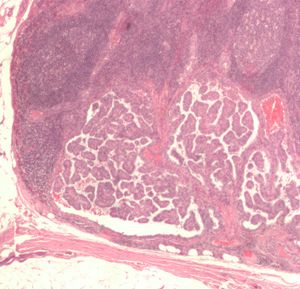

صورة مجهرية (عرض عالي الطاقة) من حليمي سرطان الغدة الدرقية مما يدل على ملامح التشخيص (المقاصة النووية ونوى المتداخلة). صبغة الهيماتوكسيلين والأيوزين. | |